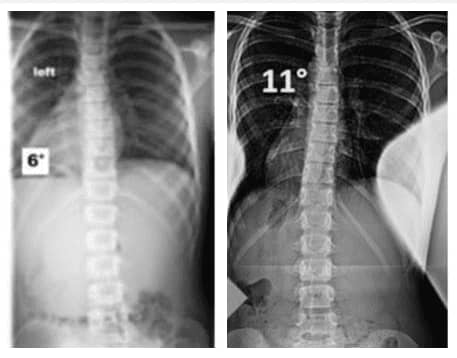

آشنایی با انواع درجات اسکولیوز

انواع اسکولیوز را بر اساس شدت انحنای ستون فقرات به صورت زیر دسته بندی می کنند:

۱. اسکولیوز خفیف:

اگر زاویه انحنای ستون مهره ها بیش از ۱۰ درجه باشد، اسکولیوز خفیف است.

۲. اسکولیوز متوسط:

انحنای ستون فقرات اگر بیش از ۲۵ درجه و قابل توجه باشد، شدت بیماری متوسط ارزیابی می شود.

۳. اسکولیوز شدید:

در اسکولیوز شدید زاویه انحراف اگر بالای ۴۵ درجه است و معمولاً به درمانهای جراحی نیاز دارد.

عکس اسکولیوز خفیف

در اینجا می توانید عکس اسکولیوز خفیف و میزان انحراف ستون مهره را ببینید: